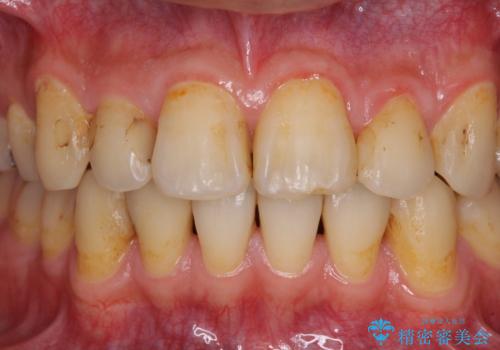

- 以前矯正を行った際に前歯が虫歯だらけとなり、審美面を気にして来院された患者様です。

虫歯の大きかった左右犬歯はオールセラミッククラウンで補綴治療をおこない、4前歯は研磨や古い充填物の詰め直しを行いました。